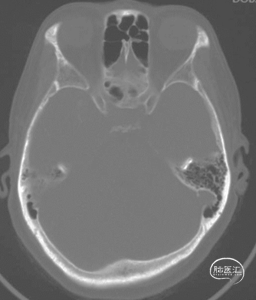

颅底CT骨窗

右侧视神经管未见明显扩大